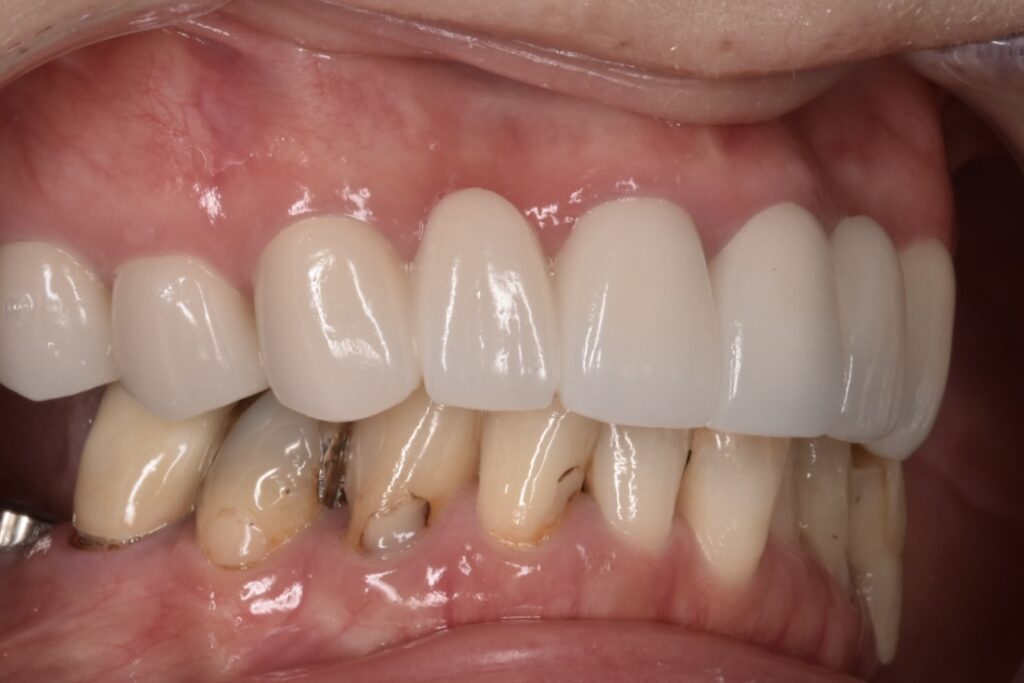

上顎セラミック治療後

上の両奥歯3本ずつはさくらセラミックプラン 前歯6本匠セラミックプランで治療させて頂きました。

セラミック本留前の仮歯でのレントゲン写真です。下の歯は破折があり抜歯してインプラントをしています。